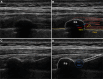

Background: Traumatic rib fractures are associated with pain lasting weeks to months and a decreased ability to inspire deeply or cough to clear secretions. Ultrasound-guided percutaneous cryoneurolysis involves reversibly ablating peripheral nerve(s) using exceptionally low temperature with a transdermal probe, resulting in a prolonged nerve block with a duration measured in months. The authors hypothesized that cryoneurolysis would improve analgesia and inspired volume after rib fracture.

Methods: Adults with one to six traumatic rib fractures were randomized to either active cryoneurolysis and sham peripheral nerve block or sham cryoneurolysis and active peripheral nerve block in a participant/observer-masked fashion. The primary endpoint was the maximum inspired volume the day after the procedure as measured with an incentive spirometer.